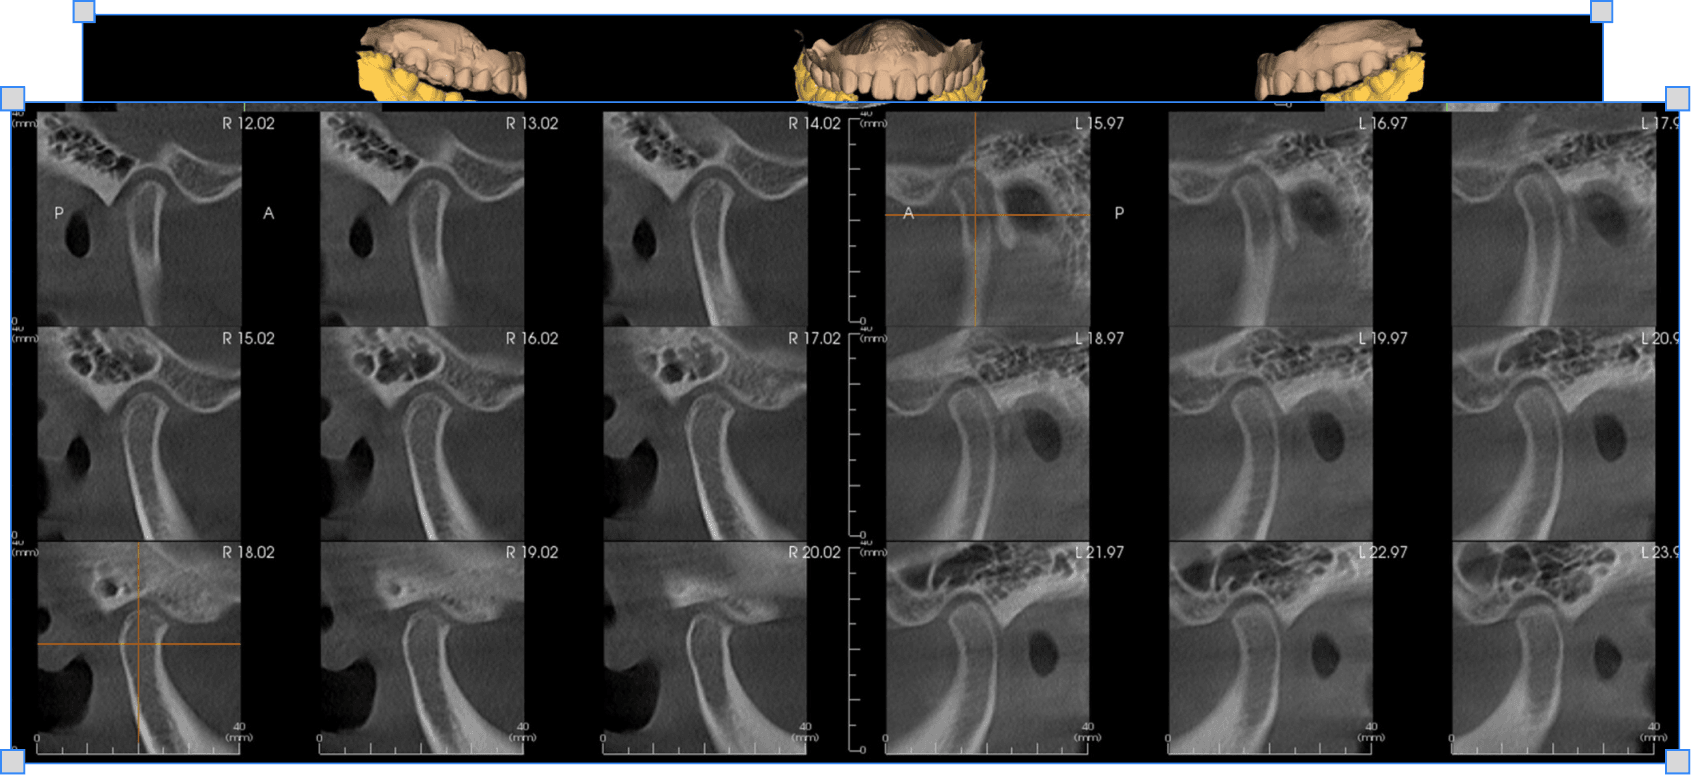

Ознаки бруксизму і дисфункції СНЩС, пальпація і міографія, воскова реєстрація щоб реставрація не дестабілізувала суглоб

Як оцінювати м'язи і суглоб пальпаторно

Що і де перевіряти без апаратури щоб зрозуміти є м'язева чи суглобова дисфункція

→ Розумієш чи є дисфункція і наскільки вона суглобова

Як діагностувати м'язевий дисбаланс міографією

Що показують графіки міографа і як читати IMPACT-індекс щоб зрозуміти яка сторона перевантажена

→ Знаєш яка сторона перевантажена і де не вистачає висоти